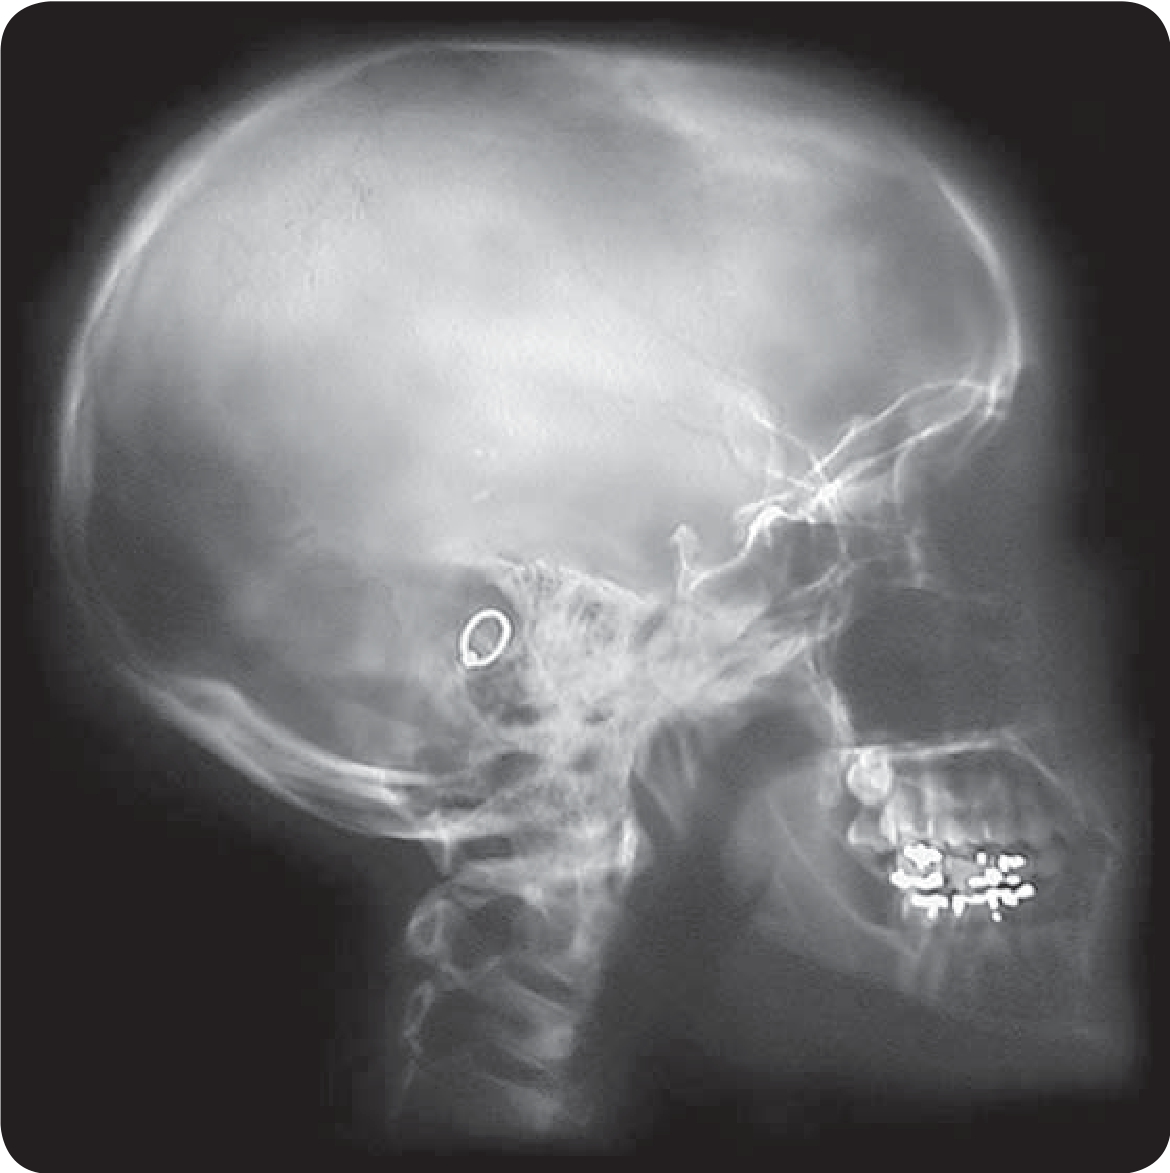

头骨的X光片

19世纪末20世纪初物理学的三大发现:X射线、放射线、电子,这一发现标志着现代物理学的产生。X射线位于三大发现之首,当伦琴发现X射线后仅仅几个月时间内,它就被应用于医学影像。1896年2月,苏格兰医生约翰·麦金泰在格拉斯哥皇家医院设立了世界上第一个放射科。放射医学是医学的一个专门领域,它使用放射线照相术和其他技术产生诊断图像,这可能是X射线技术应用医用X线机最广泛的地方。X射线的用途主要是探测骨骼的病变,但对于探测软组织的病变也相当有用。常见的例子有胸腔X射线,用来诊断肺部疾病,如肺炎、肺癌或肺气肿;而腹腔X射线则用来检测肠道梗塞、自由气体及自由液体。

通过拍X光片,我们可以看到自己的骨骼、韧带、器官、病变部位等情况,这是什么诊断原理呢?X射线应用于医学诊断,主要依据X射线的穿透作用、差别吸收、感光作用和荧光作用。由于X射线穿过人体时,受到不同程度的吸收,如骨骼吸收的X射线量比肌肉吸收的量要多,那么通过人体后的X射线量就不一样,这样便携带了人体各部密度分布的信息,在荧光屏上或摄影胶片上引起的荧光作用或感光作用的强弱就有较大差别,因而在荧光屏上或摄影胶片上将显示出不同密度的阴影。根据阴影浓淡的对比,结合临床表现、化验结果和病理诊断,即可判断人体某一部分是否正常。于是,X射线诊断技术便成了世界上最早应用的非创伤性的内脏检查技术。